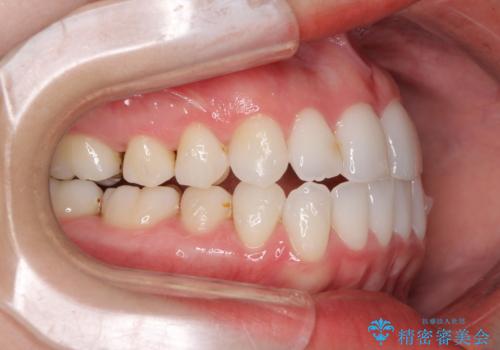

- 前歯のデコボコとクロスバイトを治したいとのことで来院された患者様です。

上下顎ともに歯列全体の側方拡大とIPR(歯と歯の間を削る)によってデコボコとクロスバイトが解消するように設計し、インビザラインにより治療を行うこととしました。

下顎骨の左側への骨格的なずれが強く、上下の正中の位置合わせや奥歯の咬み合わせ構築に苦労しました。